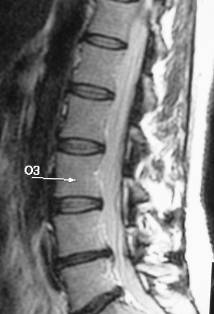

| MR image of spine one year after treatment for a herniated

disc |